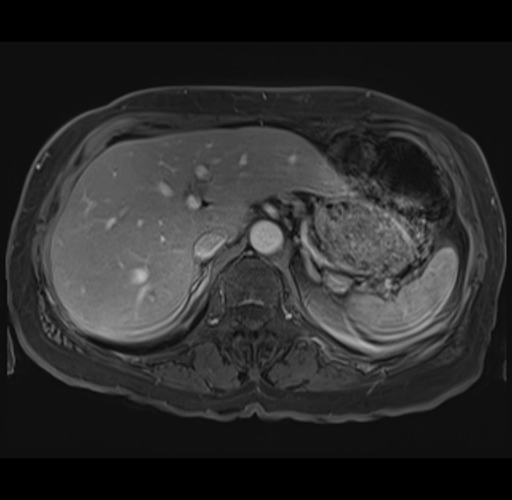

MRI T1